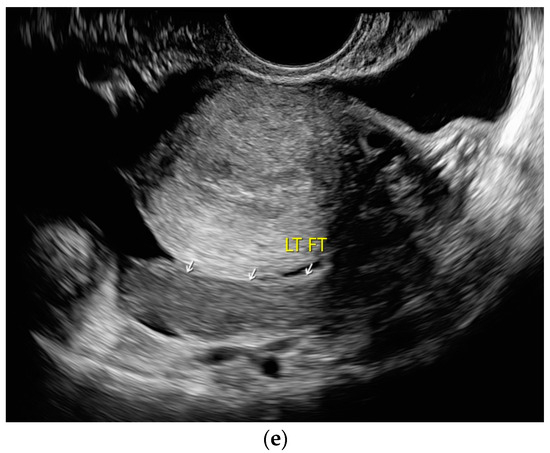

13.2. Adnexa, Fallopian Tubes, Uterus

Signs of tuberculosis in abdominal or vaginal ultrasounds in the female genital area are ovarian cyst, tubo-ovarian mass, hydrosalpinx, pyosalpinx, adhesion, adnexal fixation, thin endometrium, endometrial fluid, endometrial calcification, endometrial synechiae (Asherman’s syndrome), cornual synechiae, disturbed endometrial vascularity, ascites in the small pelvis, and peritoneal or omental thickening [122]. In a study with 175 infertile patients, ovarian cysts (23.4%) and tubo-ovarian masses (15.4%) were the most common manifestations [122] [Figure 8a–e].

Figure 8.

Tuberculosis of the uterus and adnexae. Female patients with tuberculosis in India. Pelvis with tubo-ovarian masses: Hypoechoic lesion in right adnexa (arrows) (a) and hypoechoic lesion in left adnexa and a small amount of free fluid (arrows) (b). Free fluid in the Douglas space (arrows) (c). Thickened right fallopian tube (RT FT) (arrows) (d); thickened left fallopian tube (LT FT) (arrows) (e).